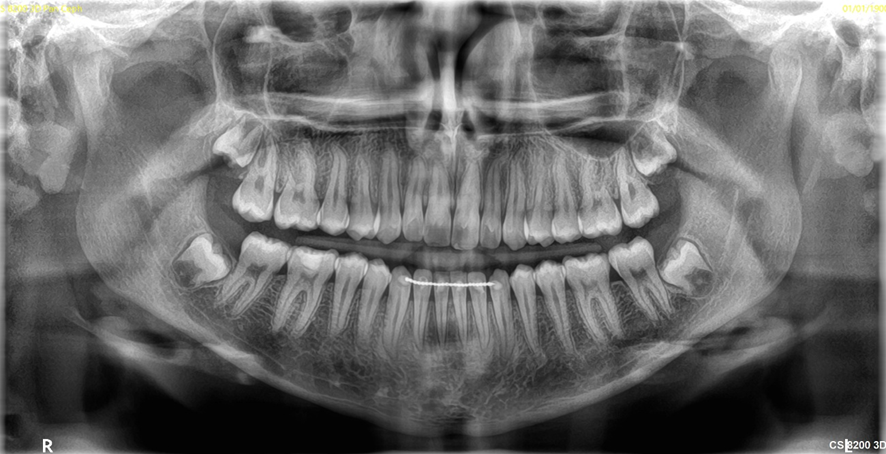

画像の鮮鋭度が大幅に向上した結果、従来のレントゲン装置に比べて、より鮮明に、よりはっきりと映し出します。

その結果、歯周病や虫歯の診断技術が大きく向上しました。

歯像処理性能が大幅にUPし、より正確な画像を再現できるようになりました。

従来のレントゲン装置では、金属のかぶせ物に放射線が反射する事により、画像が大きく乱れてしまっていました。

当院のレントゲン装置は、かぶせ物による放射線の反射(アーチファクト)を極限まで下げられる機能を有しています。

従来のレントゲン装置では撮影範囲が限られており、一部分しか撮影する事が出来ませんでした。

当院のレントゲン装置は、顎の骨全てを含む範囲までワンスキャンで撮影可能で、

また撮影範囲を選択する事も可能です。